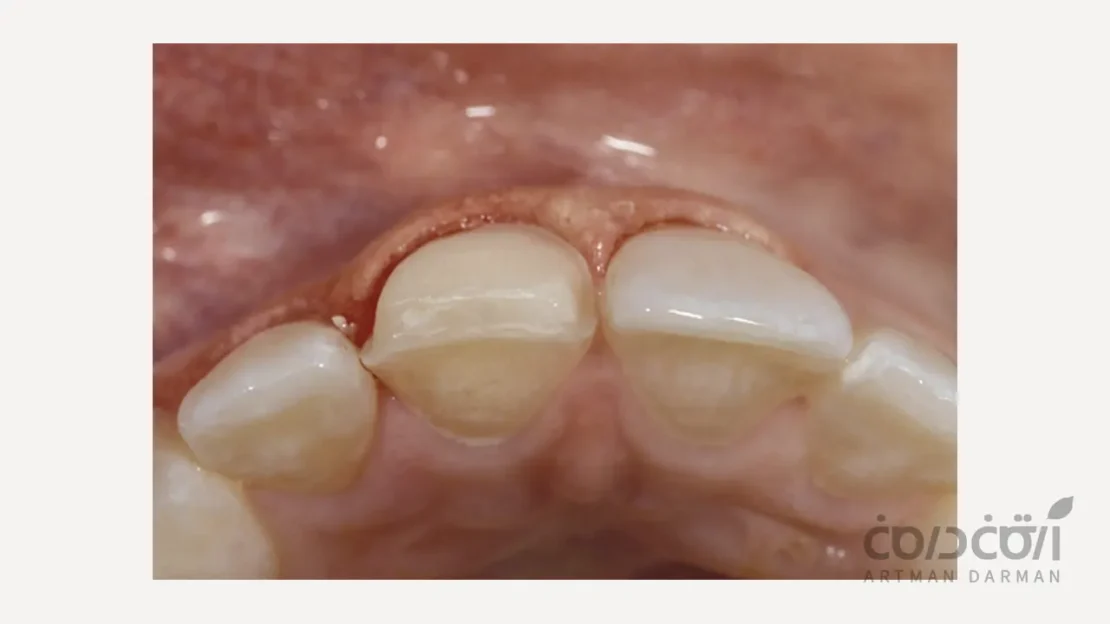

فرآیند تراش دندان برای لمینت، یک مرحله دقیق و کنترلشده است که با هدف حفظ حداکثری بافت سالم دندان انجام میشود. در نخستین گام، دندانپزشک پس از بررسی طرح لبخند و تعیین شکل نهایی لمینت، میزان تراش مورد نیاز را با دقت مشخص میکند. سپس با استفاده از ابزارهای ظریف، لایهای بسیار نازک از مینای سطح جلویی دندان تراشیده میشود تا فضای لازم برای قرارگیری لمینت ایجاد گردد. در این مرحله، ضخامت تراش معمولاً کمتر از یک میلیمتر است و تنها بخشهای ناهموار یا برجسته سطح دندان اصلاح میشوند. پس از اتمام تراش، سطح دندان پالیش و تمیز میشود تا برای قالبگیری دقیق و ساخت لمینت آماده گردد. این مراحل به گونهای طراحی شدهاند که زیبایی، استحکام و سلامت دندان تا حد ممکن حفظ شود.

تراشیدن نادرست یا بیش از اندازه دندان، میتواند بر نتیجه نهایی لمینت و سلامت طولانیمدت دندان تأثیر منفی بگذارد. اگر عمق تراش بیش از حد باشد و به لایه عاج برسد، ممکن است دندان دچار حساسیت شدید به گرما و سرما شود یا در آینده نیاز به درمانهای ترمیمی پیچیدهتر پیدا کند. از سوی دیگر، تراش ناکافی یا ناهمگون باعث میشود لمینت روی دندان به درستی ننشیند، در لبهها برجستگی یا فاصله ایجاد شود و احتمال شکستن یا جدا شدن آن افزایش یابد. در مواردی نیز تراش غیردقیق میتواند موجب التهاب لثه، گیر غذایی و تغییر رنگ در مرز بین دندان و لمینت شود. به همین دلیل، دقت در طراحی تراش و اجرای صحیح آن توسط متخصص ترمیمی و زیبایی، نقش کلیدی در ماندگاری و زیبایی نهایی لبخند دارد.